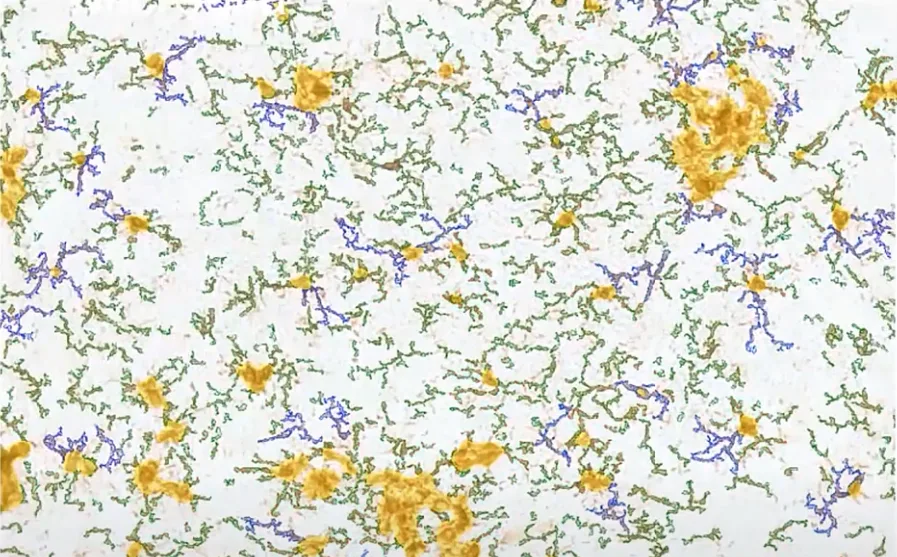

Dr. Henning Ulrich (University of Sao Paulo) presents tissue cytometry in neuroscience, showcasing applications in Alzheimer’s disease models, amyloid plaques, and neuroinflammation research.

In the next issue of TG Academy Webinars, Dr. Henning Ulrich, University of Sao Paulo, talks about applications of tissue cytometry in neuroscience and cell biology. He presents his research on amyloid plaques and neuroinflammation in an Alzheimer’s disease APP/PS1 mouse model, and shows other examples in cell biology.